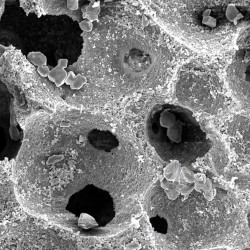

Maxresorb® inject es una pasta ósea sin endurecimiento y lista para el uso compuesta de gel de nano-HA de base acuosa y partículas de Maxresorb®. Debido a su composición específica, las propiedades viscosas de maxresorb® inject permiten una forma, moldeado y ajuste perfectos y una completa adhesión a la superficie ósea circundante del defecto.

Viscosidad y moldabilidad

Debido a su carácter viscoso que no endurece Maxresorb inject se moldea fácilmente en el lugar del defecto. Se adapta a los contornos de la superficie y proporciona el máximo contacto óseo.

Maxresorb® inject es una pasta ósea sin endurecimiento y lista para el uso compuesta de gel de nano-HA de base acuosa y partículas de Maxresorb®. Debido a su composición específica, las propiedades viscosas de maxresorb® inject permiten una forma, moldeado y ajuste perfectos y una completa adhesión a la superficie ósea circundante del defecto.

Viscosidad y moldabilidad

Debido a su carácter viscoso que no endurece Maxresorb inject se moldea fácilmente en el lugar del defecto. Se adapta a los contornos de la superficie y proporciona el máximo contacto óseo.

Biofuncionalidad

Las partículas de nano-HA, ofrecen una superficie muy grande para las interacciones celulares y son rápidamente reabsorbibles.

El componente nano-HA, que representa aproximadamente el 80% del material, se reabsorbe en un plazo de 6-8 semanas.

Los gránulos maxresorb ayudan a mantener el volumen a lo largo del tiempo.

Maxresorb inject es una masilla ósea sin endurecimiento que promueve una rápida regeneración ósea mediante el crecimiento interno de vasos sanguíneos y células a través de su estructura porosa.